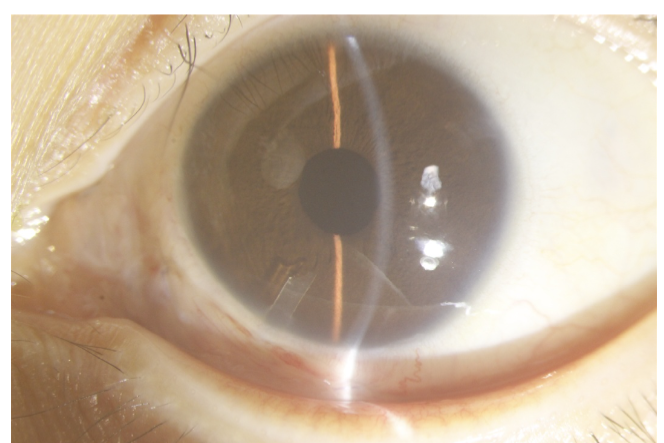

每年3月6日是世界青光眼日,今年3月10日—3月16日是第17个世界青光眼周,本次主题:共管慢病青光眼,留得光明恒久远。东莞光明眼科医院青光眼科副主任医师陈奕辉表示,青光眼是不可逆性致盲眼病,除了保持良好的生活习惯和用眼习惯外,患者每年定期检查眼压必不可少。出现眼睛胀疼、视力下降、看东西出现“彩虹光晕”等情况时,立刻前往专业的医院就诊。 01 借右眼失明经验,左眼就诊及时 “我儿患有1型糖尿病,被并发症折磨了多年,现在眼睛都看不见了,他今年才25岁,之后怎么办啊。”王某母亲眼中闪烁着泪光。陈奕辉给王某进行了专业的眼科检查,发现王某的右眼无光感;左眼视力0.25,眼压68mmHg(正常眼压在10-21mmHg),门诊诊断为“左眼新生血管性青光眼”并收入院治疗。 “你这是在高血糖的状态下,眼部发生一系列的病变,导致眼压升高,进而引起青光眼。”陈奕辉解释道。青光眼是一组以视神经凹陷性萎缩和视野缺损为共同特征的疾病,病理性眼压增高是其主要危险因素,是全球第一位不可逆性致盲眼病。 早发现早治疗是青光眼防治的关键。“我的右眼就是多年前因青光眼而导致失明的,之前发病没有重视,想着多休息就好了,结果越来越严重,后面去医院已经晚了,右眼失明且无法复明。”王某对此很懊悔,“这次吸取了右眼的经验,及时就医。” 02 引流阀植入术开辟“新通道” 青光眼一经诊断,往往需立即治疗。陈奕辉表示:“治疗青光眼的目的是有效和及时地控制升高的眼压,阻止视神经进一步损害。但目前各种治疗措施主要起到降低眼压的作用,已经发生的视神经损害无可挽回。” 患者左眼术前(左)和术后(右)眼部情况对比 青光眼如何治疗?青光眼可以通过药物、激光、手术等方式治疗。手术方式虽有多种,但手术目的都是为了打开眼球内房水循环的新通路。“根据检查结果显示,王某眼球情况特殊,正常手术的部位均发生粘连。”陈奕辉介绍道,“经讨论,决定在鼻下方行左眼青光眼引流阀植入,难度较大。”但在陈奕辉精湛的手术技术下,王某的手术顺利,左眼眼压降至17mmHg,术后恢复较好。 患者需保持良好的生活习惯 “青光眼患者需要终身治疗和随诊,但部分患者因对疾病认识不足而影响治疗。”陈奕辉提到,部分患者会因为使用眼药水“无法提高视力”,或使用降眼压眼药水“感觉不舒服”等原因而自行停药,等视力降至影响生活时再来检查,已经无法挽救已受损的视功能。 副主任医师陈奕辉给患者做手术中 因此,陈奕辉建议青光眼患者应定期检查,每月至少一次到医院测量眼压,每3月做一次全面检查,尤其是视力、视野、视盘的检查;注意观察眼睛情况变化,突然剧烈眼痛、头痛伴恶行呕吐,或视力下降、视物模糊,或其他自觉症状严重不适时,请及时就诊。 高危人群建议定期检查 青光眼早期难以发现。一旦发现眼胀、眼痛、视物不清,伴有头痛、恶心、呕吐等症状时,及时就医。陈奕辉表示,除了糖尿病会继发青光眼外,高度近视、40岁以上、有家族青光眼病史、高血压、眼外伤病史、高眼压等人群也是青光眼高危人群,建议每年到医院接受眼健康检查,监测眼压和视野。 最后,陈奕辉介绍了手指自测眼压的小方法:“眼睛向下看,以两手食指尖置于上睑,交替按压眼球,借指尖触测,若眼球硬度同鼻尖,则说明眼压正常;眼球硬度同额头,则眼压较高;眼球硬度同嘴唇,则眼压较低。”